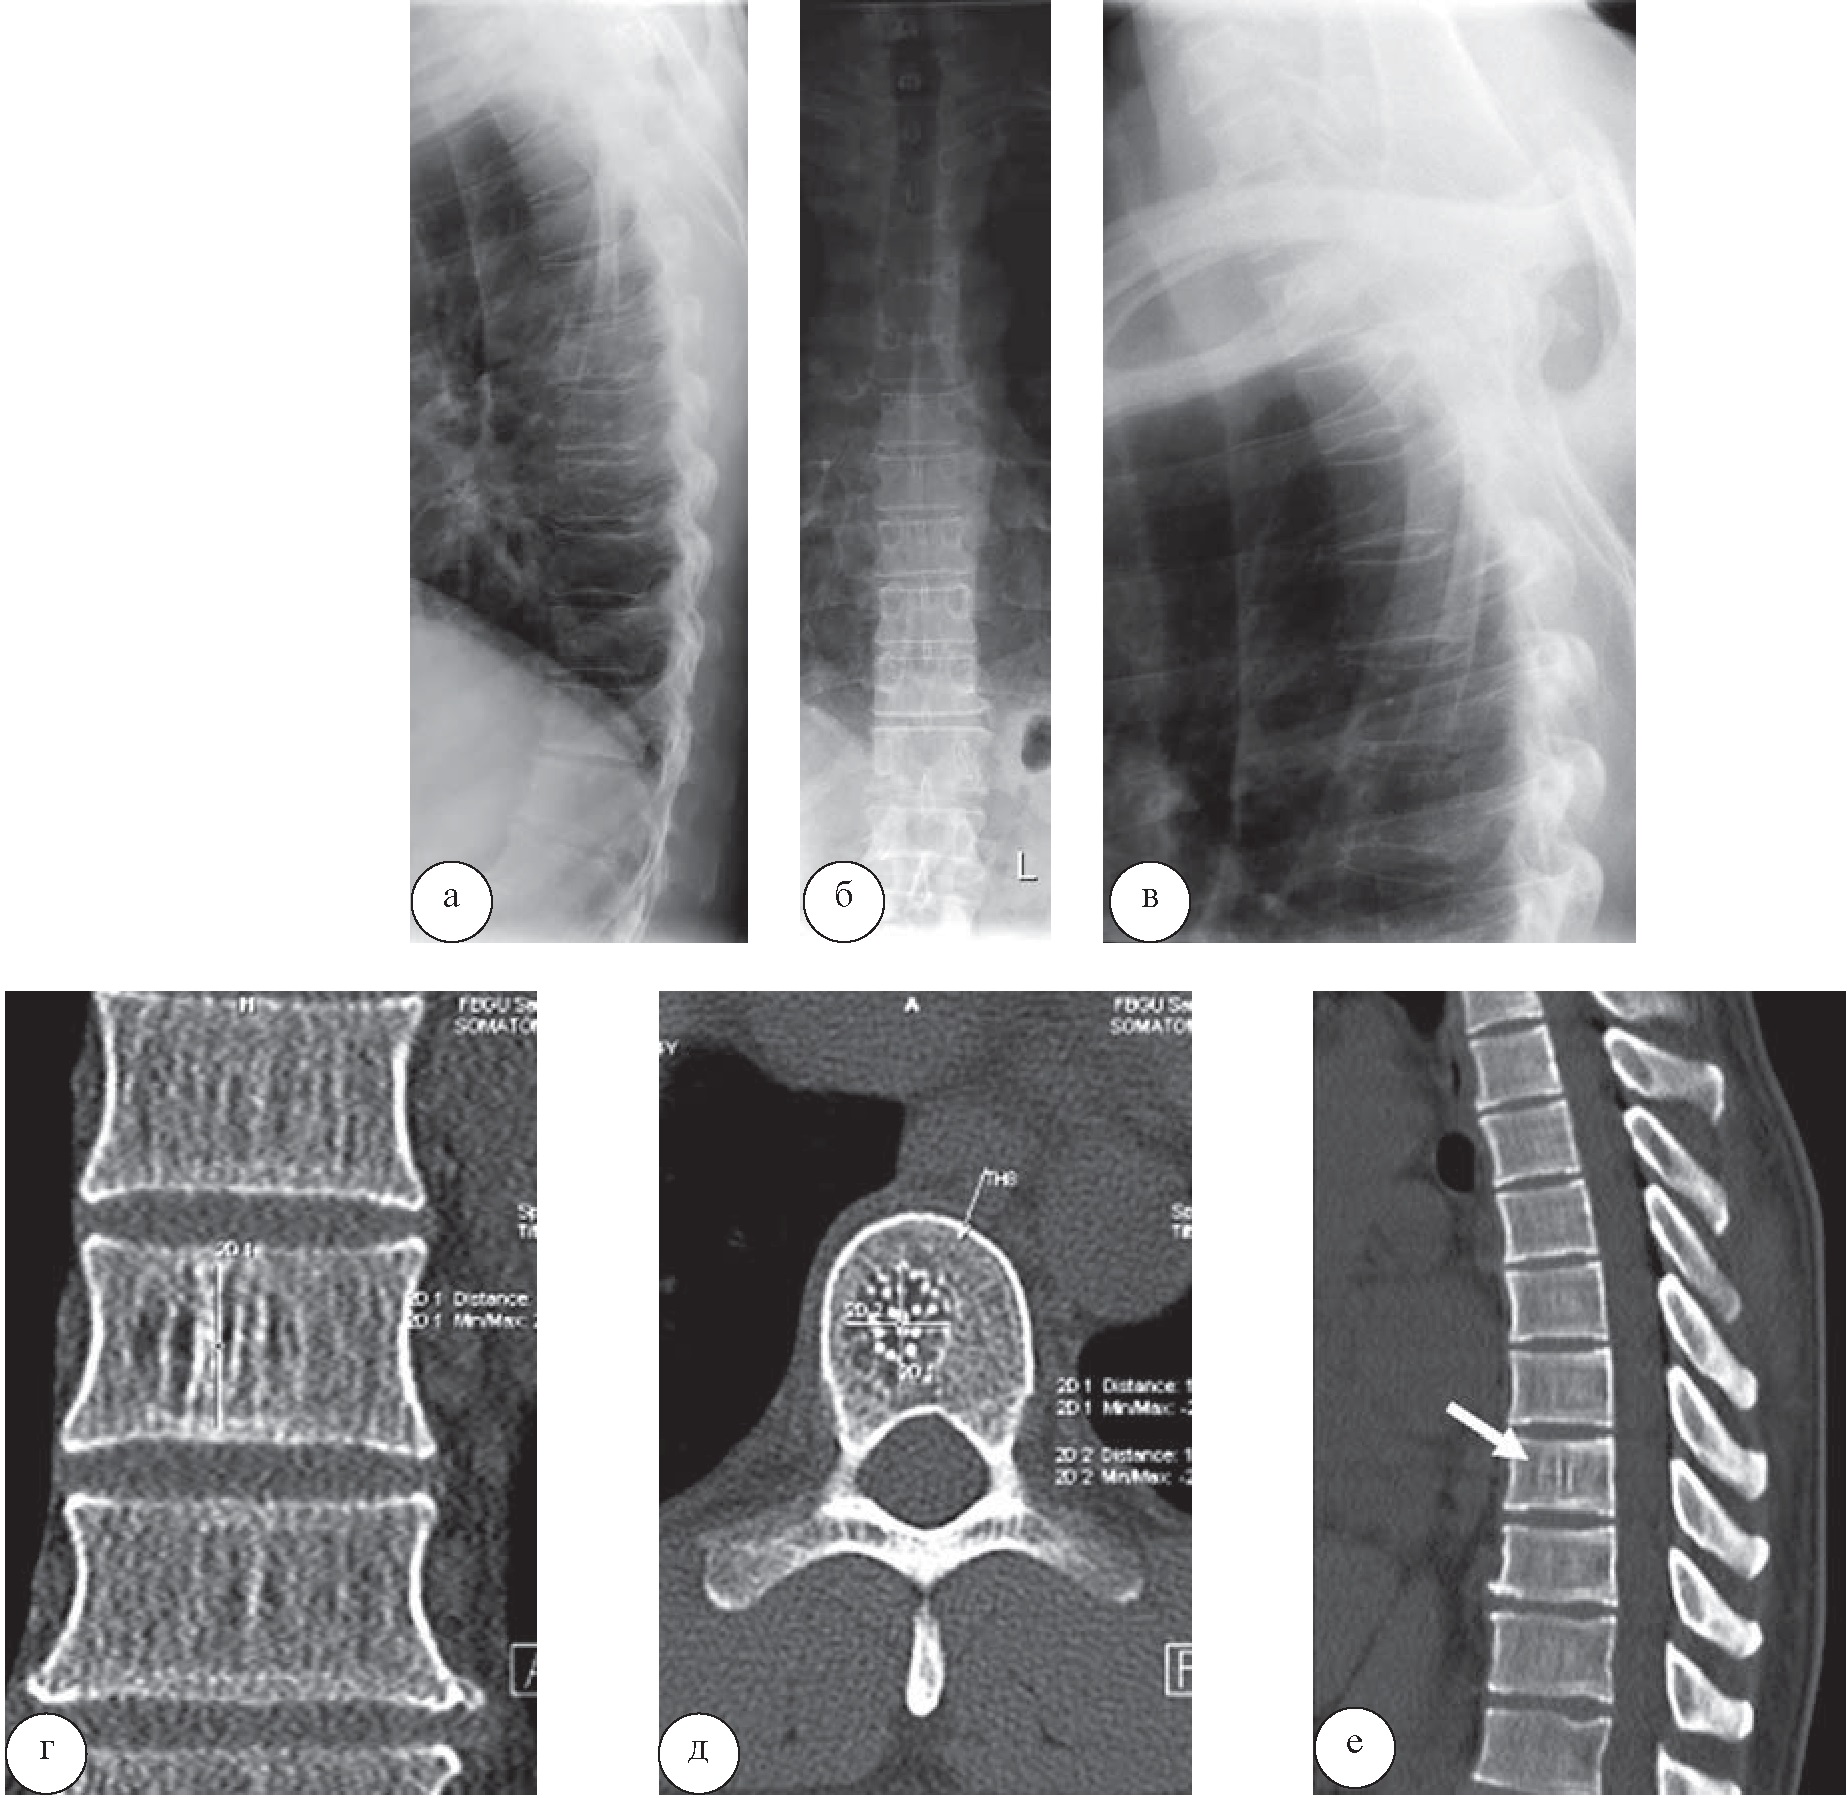

Ещё в одном случае пациент был направлен на санаторное лечение с диагнозом «остеохондроз грудного отдела позвоночника», в санаторной карте были отражены только данные рентгенологического исследования (рис. 3 а–в). При выполнении КТ (рис. 3, г–е) с целью уточнения характера и степени выраженности дегенеративных изменений было диагностировано наличие крупной гемангиомы в теле Тh8 позвонка, о которой ранее известно не было, что явилось причиной отмены электротерапии и высокочастотной терапии, тепловой терапии на данную область. Назначены массаж, вертикальное подводное вытяжение, ЛФК и кинезотерапия в общей группе, плавание.

Рис. 3. Больной Д., 34 года. При рентенографии грудного отдела позвоночника в прямой и боковых проекциях (а, б, в) определяются умеренные проявления остеохондроза грудного отдела позвоночника. На КТ во фронтальной (г), аксиальной (д), сагиттальной (е) плоскостях определяется умеренный остеохондроз грудного отдела позвоночника, остеоартроз реберно-позвонковых сочленений, гемангиома тела позвонка Th8